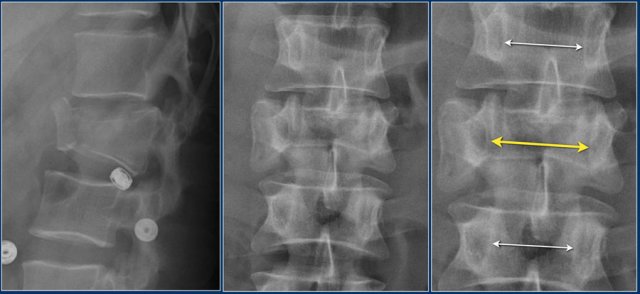

Here a fracture that just looks like another compression fracture on the lateral view.

At first glance the AP-view doesn't look very odd. That is until we zoom in and look at the distance between the spinous processes.

Now when you look carefully at the lateral view, you will notice that the facets are separated.

The MRI tells us the whole story.

You can see the edema related to the fracture of the vertebral body and the massive edema in the paraspinous muscles.

There is major disruption of the PLC of both the ligamenta flava and the interspinous ligament.

TLICS: distraction injury + PLC disruption.

This is an interesting case since non-surgical management was initially attempted in this patient.

However when we classify according to the TLICS-score, we give 4 points for the morphology and 3 points for the PLC.

Assuming the neurological exam was normal, this patient would still get 7 points.

Unfortunately, but not unexpectedly, conservative management failed with near-dislocation.

Finally a posterior spondylodesis was performed.